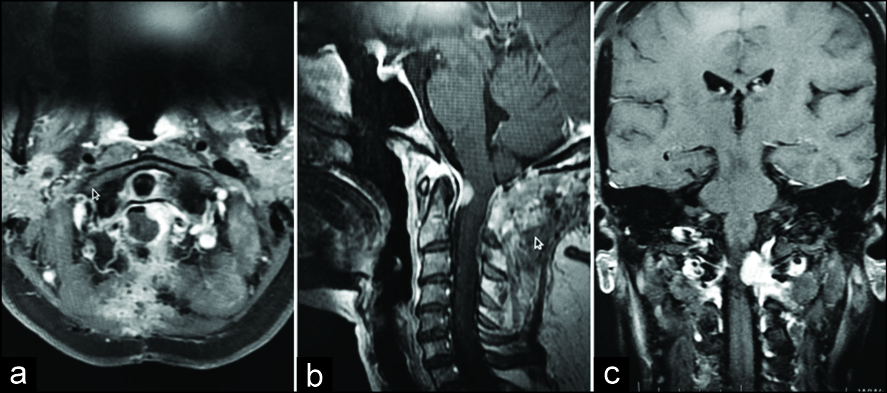

磁共振成像(MRI)顯示在椎管兩側的枕骨大孔處有明顯的分葉狀硬腦瘤,位于脊髓后外側,嚴重壓迫脊髓。病變間夾有頸髓交界處和上頸髓。對比MRI,病變顯示均勻的狂熱增強。左VA被包裹在病變內,而右椎骨被鄰接。右側測得的質量為14毫米(顱尾)×12毫米(前后)×8毫米(寬度),左側為12毫米(顱尾)×11毫米(前后)×7毫米(寬度) [ 圖1  ]。診斷為大孔鏡面腦膜瘤,并計劃切除?;颊呓邮芰薈-1后弓切除,C-2椎板切除術,大孔減壓和病變切除。腫瘤是高度血管性的,在兩側的齒狀韌帶后都有不同的硬腦膜附著。腫瘤完全在右側完全切除。但是,在切除左側腫瘤的內側部分的過程中,發(fā)現(xiàn)其附著在VA上。由于腫塊粘附在左VA上,因此以小塊的方式進行了手術切除,并關閉了硬腦膜。術后期間平穩(wěn),患者癥狀好轉。術后6個月的MRI增強掃描顯示,右側腫瘤完全清除,左側殘余病變較小[ 圖2 ]。組織病理學檢查發(fā)現(xiàn)腦膜瘤性腦膜瘤(WHO 1級)[ 圖3 ]。

術前對比增強磁共振成像(MRI)

圖1:

術前對比增強磁共振成像(MRI)圖像顯示明確定義的雙側增強病變。神經被夾在病變之間并被嚴重壓迫(a)軸性:雙孔增強的雙側大塊病變,(b)矢狀位MRI,(c)冠狀位MRI,(d)計算機斷層血管造影顯示病變與椎骨的關系動脈。